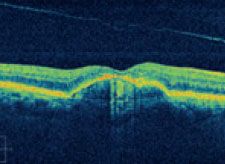

Die optische Koherenztomographie in spectral Technik (auch bekannt als „Spectralis“, Fourier Domain OCT oder 3D – OCT) ist die modernste und genauste Methode zur Darstellung von Netzhautveränderungen.

Mithilfe modernster Algorithmen und Analyseverfahren kann das Cirrus HD-OCT einzigartig detaillierte HD-Darstellungen erzeugen.

Chorioretinitis centralis serosa

- HD-OCT-Bilder sind hochauflösende Querschnitte, welche die Pathologie bis ins kleinste Detail darstellen.

- Das HD-OCT-Bild zeigt die Netzhautschichten bis ins kleinste Detail. Die genaue Position dieses Bildes ist auf dem LSO-Fundusbild angegeben.